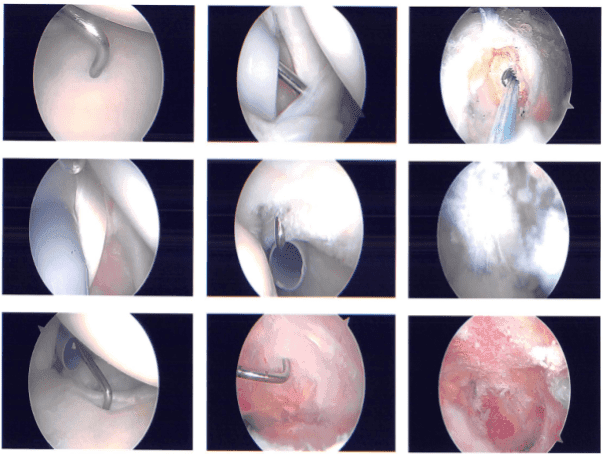

Imágenes intraoperatorias

El examen de la articulación mostró deshilachamiento del tendón subescapular con desgarro parcial. El tendón del bíceps estaba intacto. Hubo una rotura lateral articular de alta calidad en el infraespinoso del manguito rotador, que fue desbridada con el uso de una afeitadora.

El examen del labrum y la tenodesis fue muy normal. El desbridamiento del tendón subescapular se realizó mediante una afeitadora. También se realizó desbridamiento del tendón del manguito rotador. Se tomaron y guardaron fotos. El artroscopio se insertó en la bursa subacromial e introdujo una afeitadora.

Descompresión subacromial realizada. Examen de artritis. La rotura se encontraba en la región del infraespinoso, que fue desbridada. reparado. Se utilizó un ancla doble de cuatro colas Healicoil Smith & Nephew, que se insertó en el tapping.

Se usaba una sutura del ancla mucho más adelante y posterior, y se ataba con el uso de… Tras el cierre, se lograba una buena reparación del manguito rotador. La acromioplastia se realizó con el uso de la varita de coblación seguida de la muebla #6-0.

También se realizó la escisión distal de la clavícula con el uso de varita de coblación, seguida de la rebarba desde la puerta posterior y anterior. Se tomaron y guardaron las fotos finales. Luego el hombro se regó y se cubrió a fondo.